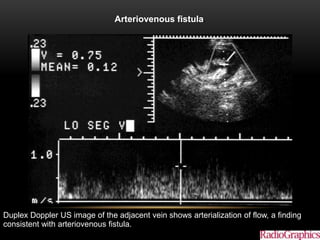

Arteriovenous fistula.

Akbar S A et al. Radiographics 2005;25:1335-1356

©2005 by Radiological Society of North America

Duplex Doppler US image of the adjacent vein shows arterialization of flow, a finding

consistent with arteriovenous fistula.

Arteriovenous fistula. Akbar SA et al. Radiographics 2005;25:1335-1356 ©2005 by Radiological Society of North America Duplex Doppler US image of the adjacent vein shows arterialization of flow, a finding consistent with arteriovenous fistula.